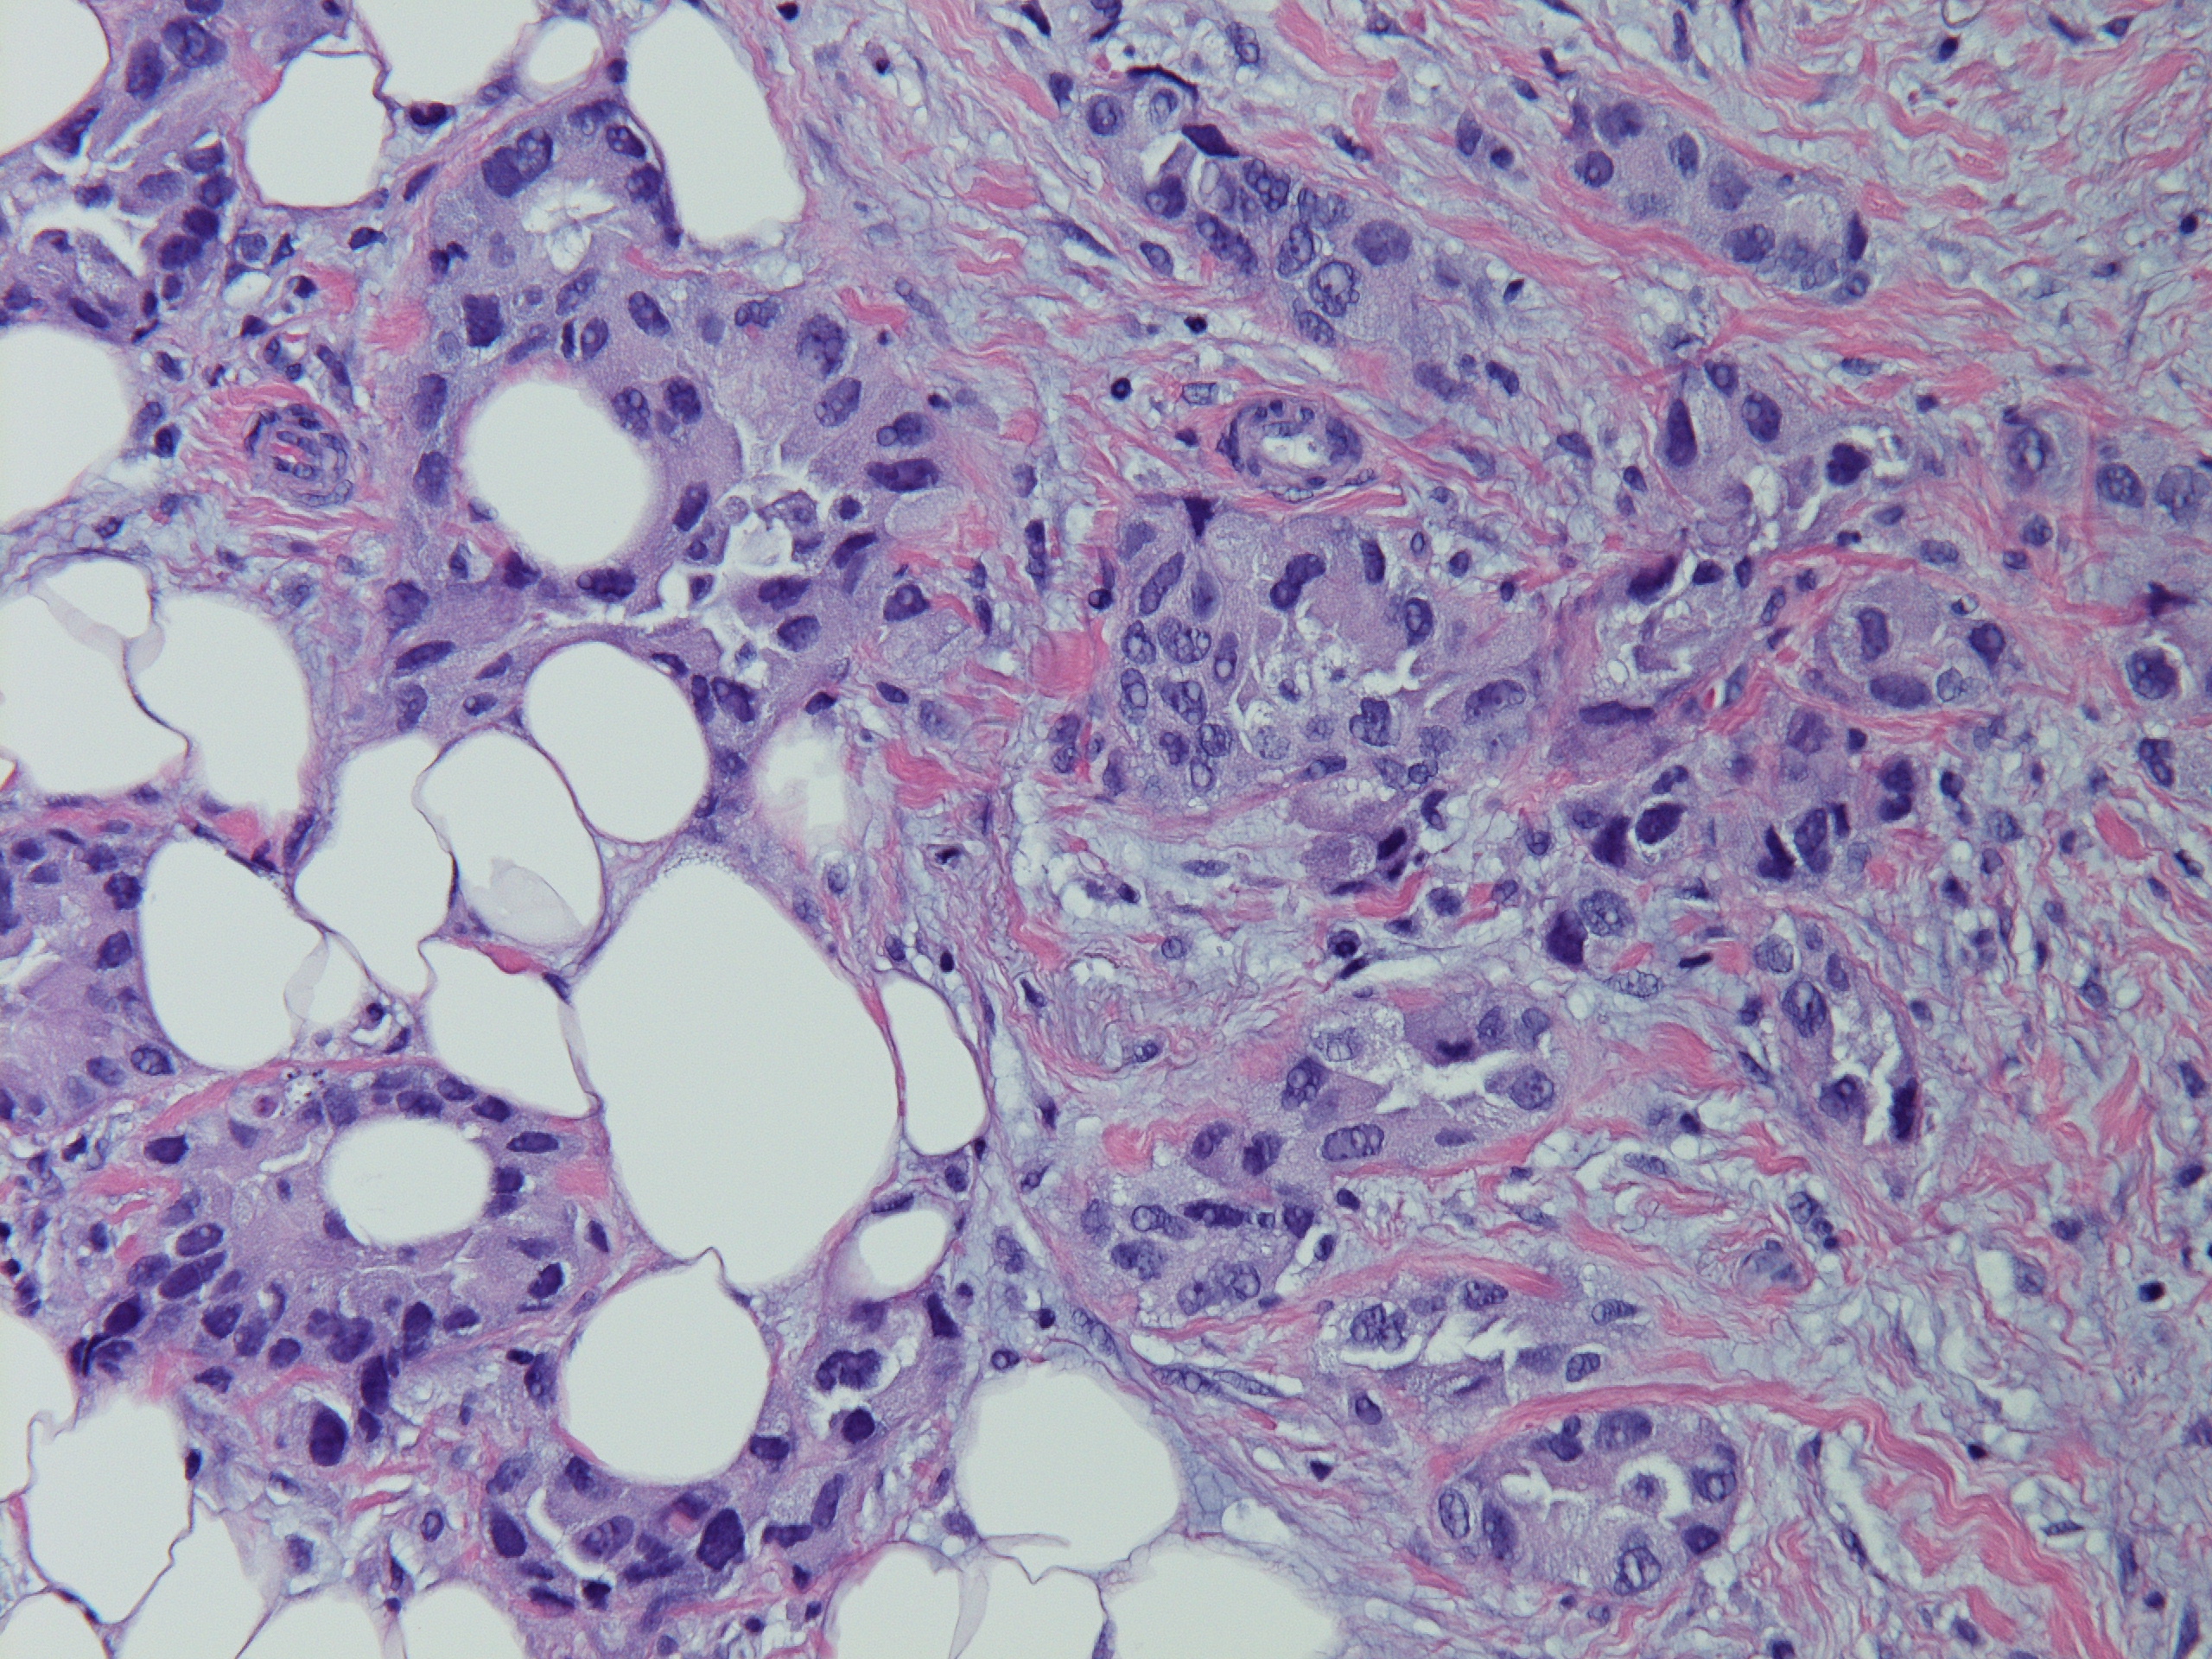

分享赵老师的一个病例:女,70岁,发现左侧乳腺肿块,2.5cm,行穿刺活检。无其他病史。

INVASIVE ADENOCARCINOMA, NUCLEAR GRADE 3.COMMENT:Multiple immunostains were ordered to determine it is a primary or metastatic tumor.

AddendumImmunostains were performed on the block. The tumor cells are positive for CK7, TTF-1, focally and weakly positive for ER, negative for PR and GATA-3, GCDFP, mammaglobin. The immunostain results support this is a metastatic carcinoma from pulmonary primary. This patient reportedly has metastatic adenocarcinoma of lung origin.AddendumNapsin A is positive, supporting a lung primary.

此例最后考虑是来自肺的转移性腺癌